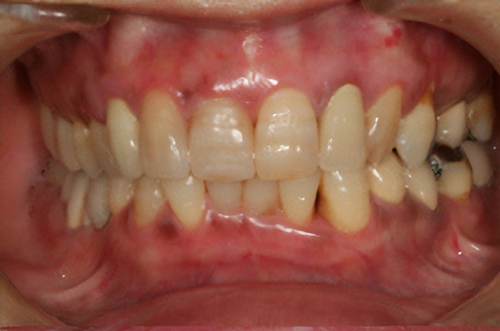

黒ずんだ歯肉の色をお薬で、キレイなピンク色の歯肉にします。

塗り薬の麻酔と薬液だけで10分程度、2回の治療でキレイなピンク色に。-

術前

術後

※ガムピーリングの効果には個人差があります。

- > 一時的に沁みることがある。

- > 個人差がある。

- > 色素が深い場合は変化しない部位が残ることがある。

副作用:一時的に歯肉が沁みることがある。1週間程度歯肉は白くなる。